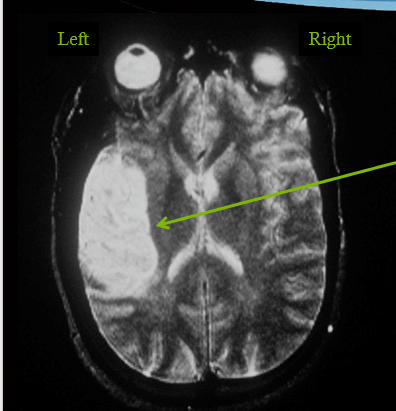

infarct in MCA territory leading to all loss of fibers losing vision on opposite side